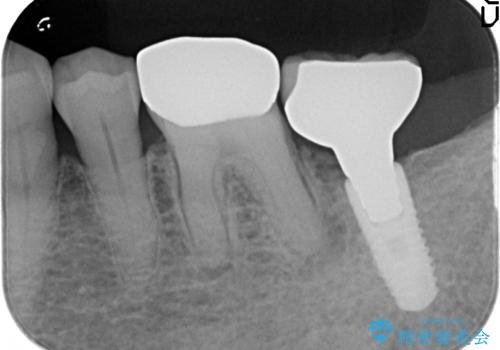

検査の結果、左下6番目の歯は神経が死んでおり根尖に病変が出来ていたため、根管治療を行いました。

その後症状の消失を確認後、オールセラミッククラウンによる補綴を行いました。